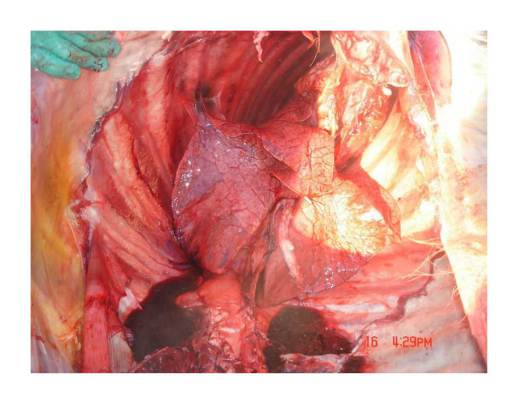

-Хэвлэлээр малчин Норсүрэнгийн 22 бяруу үхсэн гэж мэдээлдэг. Гэвч бодит байдал дээр үхсэн малын тоо түүнээс хавьгүй их, бараг өрх бүрээс төдий хэмжээний мал зүй бусаар хорогдсон ба нийт тооцоогоор 700 орчим мал үхсэн байх магадлалтай байна. Нэн ялангуяа Аревагийн ойролцоо нутагтай Аргалантын 3-р багийн малчдын мал сүүлийн 2 жилд олноор хорогджээ. Түүнчлэн мал хээл хаях, гаж төрөх явдал элбэгшиж, учир битүүлэг өвчний улмаас нийт малын нүд ѳвдөж, хүүхэн хараа нь цайсны учрыг малын эмч нар ч оношилж чадахгүй байгаа ажээ. Шинээр төхөөрсөн малын уушги, элэг нь хар цагаан толботой, цэврүүтсэн, идээ бээр гүйсэн, дотор эрхтнүүд нь сэмжтэйгээ наалдсан, тэр бүү хэл, амьгүй төрсөн хурга ишигний элэг, уушиг хүртэл толботой байх болжээ.

Дорноговь аймгийн Улаанбадрах сумын малын дотор эрхтэний зураг.